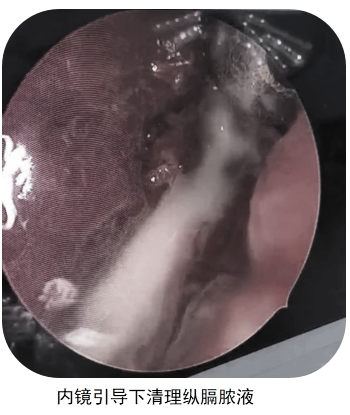

医院多学科协作,各个环节紧密相连,一路绿通:放射科完善颈、胸部增强CT联扫,精准评估了病变范围;肾病内分泌科指导降糖、消酮用药方案;在麻醉手术科全程保驾护航之下,耳鼻咽喉头颈外科完成颈部切开入路咽后及纵隔脓肿引流术;急诊手术后,ICU接手给予强效抗感染、纠正酸中毒等综合治疗。经过医护团队的严密监护与精细化救治,患者生命体征平稳后转回耳鼻咽喉头颈外科普通病房继续康复。